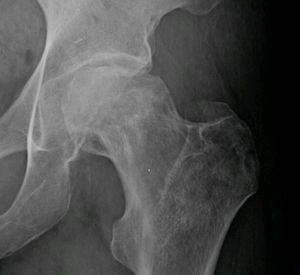

Avascular necrosis of hip

- Plain XR is poorly sensitive in early stages, as low as 41%

- AP and Frog leg views

- MRI ~90% sensitivity and specificity

- Best test